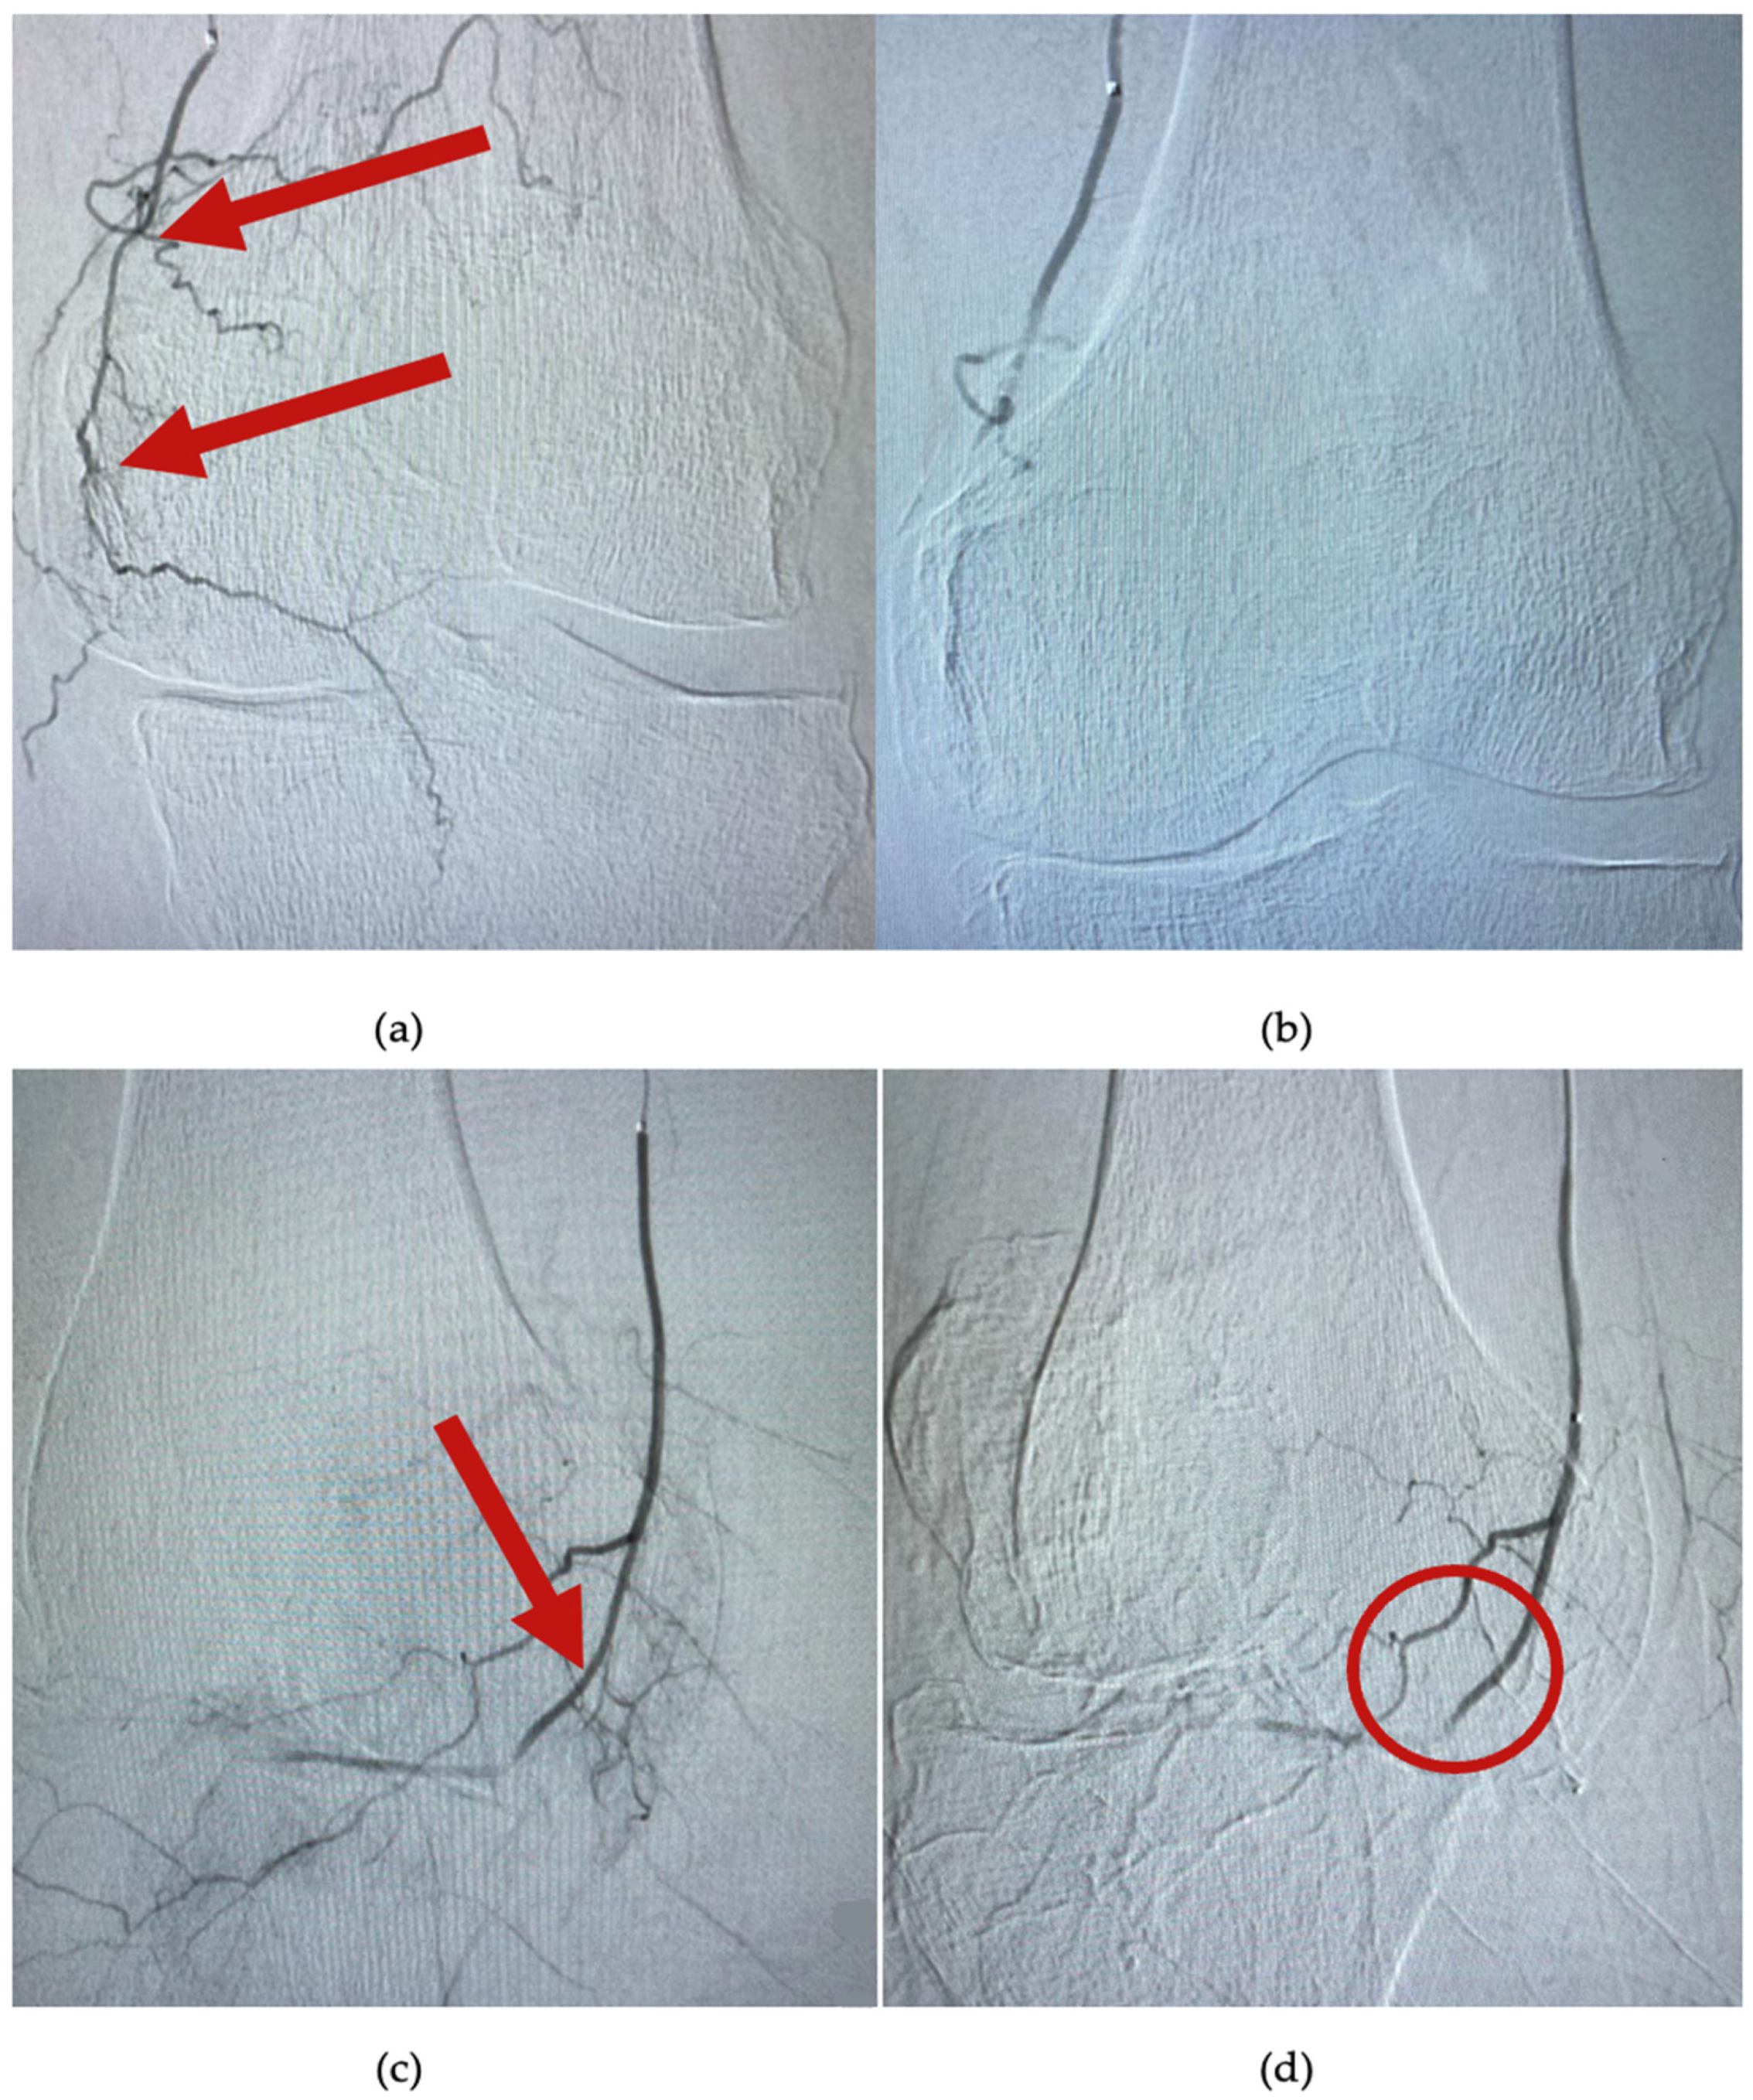

The procedure begins with the catheterization of the left brachial artery and the placing of a 5Fr catheter at the level of the superficial femoral artery. Afterwards, a selective catheterization of the superior genicular arteries (medial or lateral) is performed by using a 0.021 inch microcatheter (Direxion, Boston Scientific, Marlborough, MA, USA). Under fluoroscopic guidance, the desired genicular artery branch is identified. In total, 200 mcg of nitroglycerine is injected, and the knee is immediately iced for 10 min by using an instant cold pack of ice (Dynarex, Blauvelt, NY, USA). Then, an angiogram reveals hypervascularity with numerous capillary branches within the medial or lateral joint space, as exemplified in Figure 3a,c. A suspension with contrast substance and imipenem/cilastatin sodium (IPM/CS) (embolic agent) was injected. Distal hypervascularity was assessed fluoroscopically until it was resolved. As seen in Figure 3b,d, adequate blood flow should be maintained within the selected artery branch after deployment. A control angiogram is performed as a final step, and hemostasis is achieved by manual compression of the brachial artery. All patients were scheduled to be discharged 4 h postintervention.

Figure 3.

Angiogram at the level of the superior medial genicular artery. (a,c) are images of arterial blush (arrows), before embolization; (b) shows complete embolization and lack of the hypervascularity; and in image (d), bone and capsular branches are selectively avoided (circle).